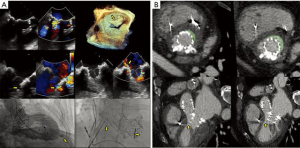

- The Paravalvular Leak Academic Research Consortium expert statement describes endpoint definitions and the role of imaging (36). For mitral paravalvular leaks (PVL), TEE overcomes the left atrial shadowing from the prosthesis seen in TTE and precisely identifies the PVL location and size, allowing planning of the procedure and adequate communication with the operator. CT may identify prosthetic annulus dehiscence, incomplete sealing after TMVR, or early dysfunction of the prosthesis due to pannus, sometimes mimicking a PVL (Figure 8). CT imaging uses careful reconstructions, selected image kernels and multiphase analysis to evaluate the anatomy of the leak and the surrounding structures. A PVL may be serpiginous and be located under, rather than adjacent to, the prosthetic ring, requiring dedicated oblique views for accurate imaging. Additionally, their area is dynamic and may seal during various phases of the cardiac cycle (Figure 13, Video 5). This phenomenon impacts the evaluation of the severity of mitral regurgitation, as the regurgitant jet may not be holosystolic and PISA may overestimate its severity. Additionally, the extent of associated hemolysis may be out of proportion to the size of the regurgitant jet, as estimated by color Doppler. In patients with mechanical prostheses, TEE may predict the risk of disk impingement by the closure device and is used to determine the size of the closure device. Guiding the procedure, cropped 3D TEE and 2D X-plane views are used to ascertain the passage of the wire through the PVL orifice. Once the device is deployed, an immediate assessment of mechanical leaflet mobility is performed, followed by a search for residual leaks, frequently under hemodynamic stress (volume challenge and pharmacological manipulation of the arterial pressure). While PVL closure traditionally relies on a transseptal approach, a transapical “Hopscotch” approach has been described recently, which also benefits from echocardiographic intraprocedural guidance in combination with CT angiography (37).